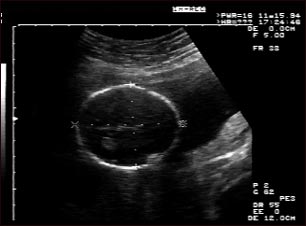

Ultrasonido de un feto normal; medidas de la cabeza

Ultrasonido normal a las 19 semanas de gestación. Por lo general los médicos prefieren disponer de las medidas fetales para verificar el tamaño del feto y para buscar anomalías. Este ultrasonido muestra las medidas de la cabeza fetal, señaladas por las líneas punteadas y las cruces.